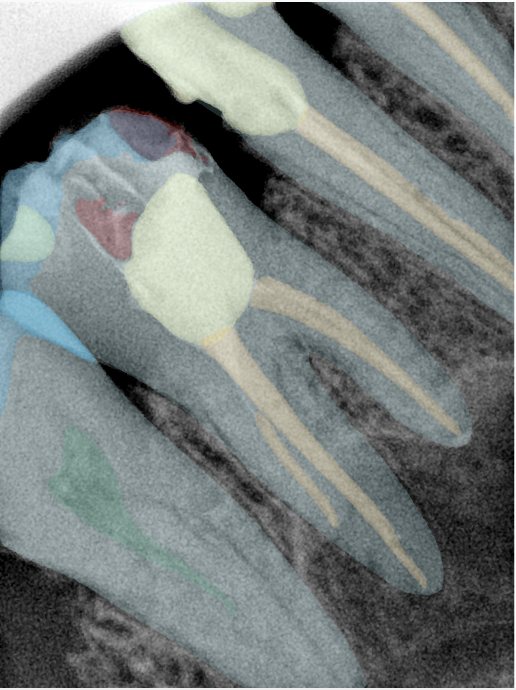

第二版算法问题测试

| 第一版 | 第二版 | 是否解决 | |

|---|---|---|---|

![]() | ![]() ![]() 边角识别有问题 龋齿识别不全 牙髓识别不全 | ![]() | 解决 |

![]() | ![]() 边角识别有问题 识别信息有误 自查(牙冠识别不全) | ![]() | 解决 |

![]() | ![]() ![]() 边角识别有误 大范围填充识别遗漏 | ![]() | 解决 |

![]() | ![]() 识别信息不全 | ![]() | 解决 |

![]() | ![]() ![]() 边角问题 牙胶识别不全 牙冠识别不全 | ![]() | 解决 |

![]() 换图片 | ![]() | ![]() 牙冠部分稍微白了一些就识别成小范围修补,部分判断异常 | 部分解决,修复类略敏感,牙冠部分稍微白了一些就识别成小范围修补,部分判断异常。 |

![]() | ![]() ![]() 牙冠识别不全 牙髓不全 根尖炎龋齿识别有误 | ![]() | 解决 |

![]() | ![]() | ![]() | 解决 |

![]() 换图片 | ![]() | ![]() | 解决 |

![]() | ![]() 牙冠识别有误 | ![]() | 解决 |

![]() 换图片 | ![]() ![]() 边角识别有误 | ![]() 修复类敏感 | 部分解决,图像过白,导致修复类判断异常。 |

![]() 换图片 | ![]() 牙冠识别不全 | ![]() 修复类敏感 | 部分解决,图像过白,导致修复类判断异常 |

结论:修复类出现了不鲁棒的情况,后续需要加入轮廓的扩充数据进行增强。